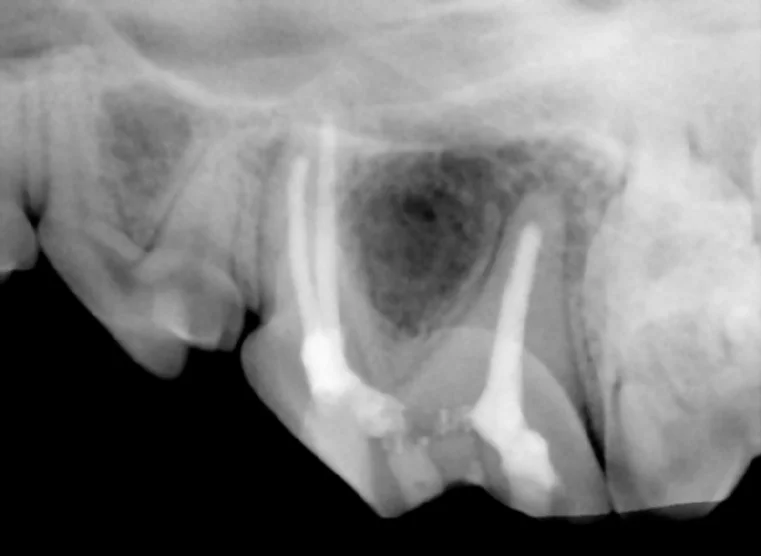

A swelling of the lower jaw was noted on a dog. On examination, no visible tooth in the area was noted. However, dental x-rays show a tooth below the gumline that was unerupted and had caused a cyst to form.